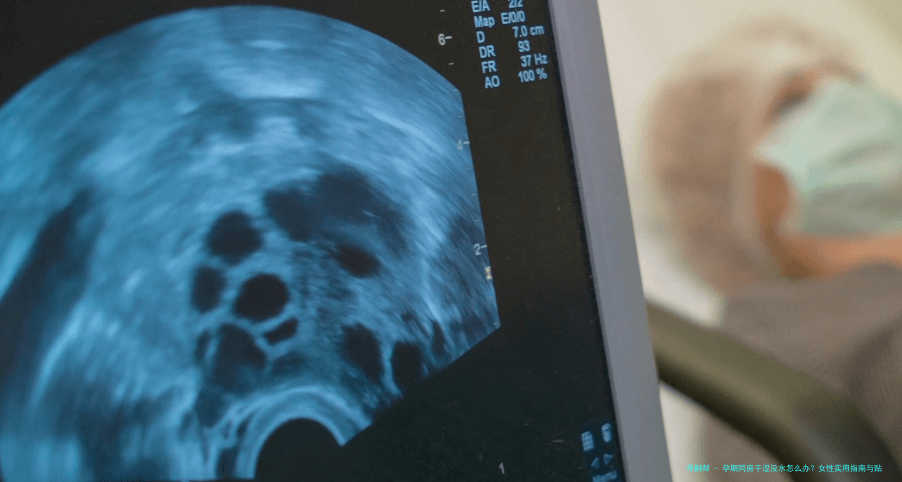

首先,咱们得明白为啥会出现这种情况。孕期身体变化大,激素水平波动是主因。雌激素和孕激素的升降,直接影响阴道分泌物的多少——说白了,激素一乱,"润滑系统"就容易罢工。据近年医学数据,超过25%的孕妇因激素变化导致阴道干涩,尤其在孕中期和晚期更明显。其次,心理因素也不能忽略;怀孕后,你可能更焦虑或疲劳,这些情绪会抑制性欲,让身体"没状态"。另外,身体不适如尿频或背痛,也会间接导致干涩。我记得有个案例,一位准妈妈因为担心伤到宝宝,心理压力大,同房时总是紧张,结果干涩问题更严重了。所以,原因多种多样,但大多是可逆的,别太自责。